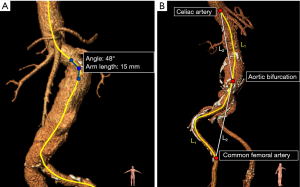

Maximum tortuosity angle: The maximum tortuosity angle of aorto-iliac segment was measured using a 3D adaption of the technique described by van Keulen et al. (10), available in the 3Mensio workstation (3Mensio Medical Imaging, Bilthoven, the Netherlands). This function measures the angulation between two line-elements of 15 mm along the central lumen line (Figure 3A). The highest angulation in the aortoiliac segment (from left subclavian artery until the origin of the common femoral artery) was recorded as maximum tortuosity angle.

Tortuosity index: The tortuosity indices of the aortic and iliac segment were calculated using a function available in the 3Mensio workstation. The aortic segment ranged from the left subclavian artery until the aortic bifurcation. The iliac segment ranged from the aortic bifurcation until the origin of the common femoral artery and was measured unilaterally on the side of stent graft introduction. The tortuosity index was calculated by dividing the distance along the central lumen line (L1) of the arterial segment, by the straight-line distance between the start and endpoint of the segment (L2) (11,12). These measurements are shown in Figure 3B.